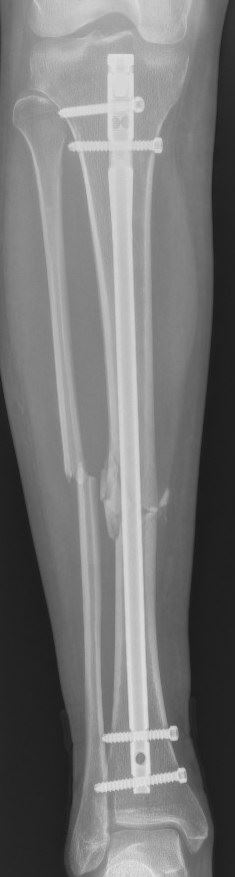

In het geval dat zowel uw scheenbeen als uw kuitbeen gebroken zijn, is het meestal voldoende om alleen uw scheenbeen vast te zetten omdat dit het sterkste bot is. Of uw kuitbeen ook moet worden vastgezet is afhankelijk van de hoogte van de breuk en de stand van de bijkomstige kuitbeenbreuk, maar dit is vaak niet nodig.

Veel gebruikt is een pen in de mergholte van het bot, die vlak onder de knie kan worden ingebracht. De pen wordt vervolgens met dwarse schroefjes aan het begin en het einde van de pen vastgezet. Een andere optie is het gebruik van platen en schroeven om de verschillende breukdelen stevig aan elkaar vast te zetten. Voor het plaatsen van een plaat is wel een grotere snede nodig dan voor een pen. Indien er sprake is van een ernstig weke delen letsel en zeker als er meerdere ernstige letsels tegelijk aanwezig zijn, kan uw chirurg er ook voor kiezen om de breuk, al dan niet tijdelijk, van buitenaf vast te zetten met een extern fixatie mechanisme (de zogenaamde ‘externe fixateur’).